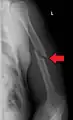

Humerus fracture

Midshaft humerus fracture with callus formation

Middle fractures are usually caused by either physical trauma or falls. Physical trauma to the humerus shaft tends to produce transverse fractures whereas falls tend to produce spiral fractures. Metastatic breast cancer may also cause fractures in the humerus shaft.[12] Long spiral fractures of the shaft that are present in children may indicate physical abuse.[5]

Fractures of the humerus shaft are most often uncomplicated, closed fractures that require nothing more than pain medicine and wearing a cast or sling. For midshaft fractures up to 12 weeks may be required for healing.[17]